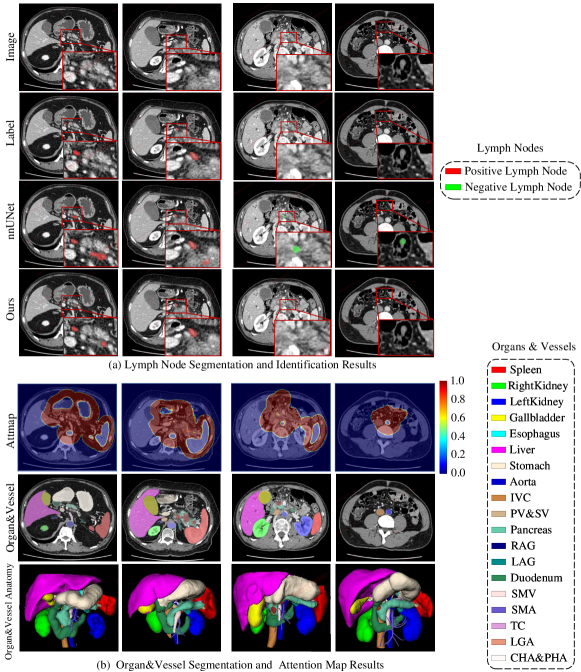

Qualitative evaluation of organvessel segmentation examples as well as the corresponding attention maps are visualized in Fig. 4 (b).

Qualitative Evaluation. Examples of LN segmentation and identification results are shown in Fig. 4 (a) for qualitative comparison. Our segmentation model leverages prior knowledge of LNs’ position distribution by incorporating the attention mechanism to remove false positives that are far from anatomically plausible LN areas. In Fig. 4 (a), we can observe that nnUNet tends to falsely detect an instance inside some organs or located very far, while our method provides noticeably less false positives.